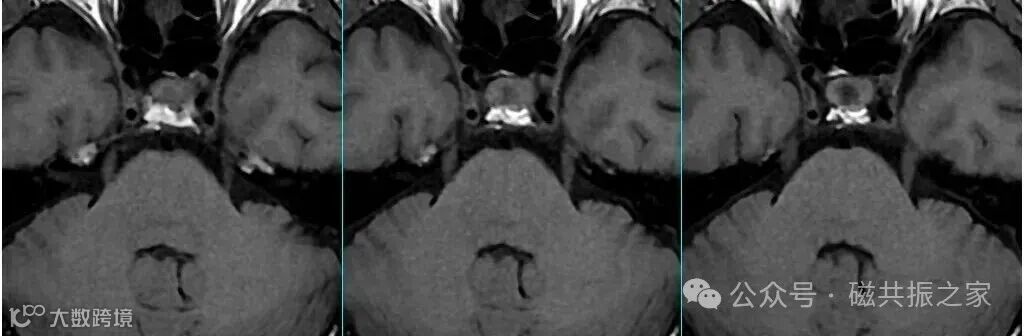

上图△展示的是采用基于自旋回波的3D T1WI所获得三叉神经的图像。

在这两个序列上血管,神经呈低信号,脑脊液呈高信号,对比明显,可显示神经精细形态结构。

如上图△,左为基于梯度回波的3D 稳态自由进动序列;右为基于自旋回波的3D 重T2WI序列。